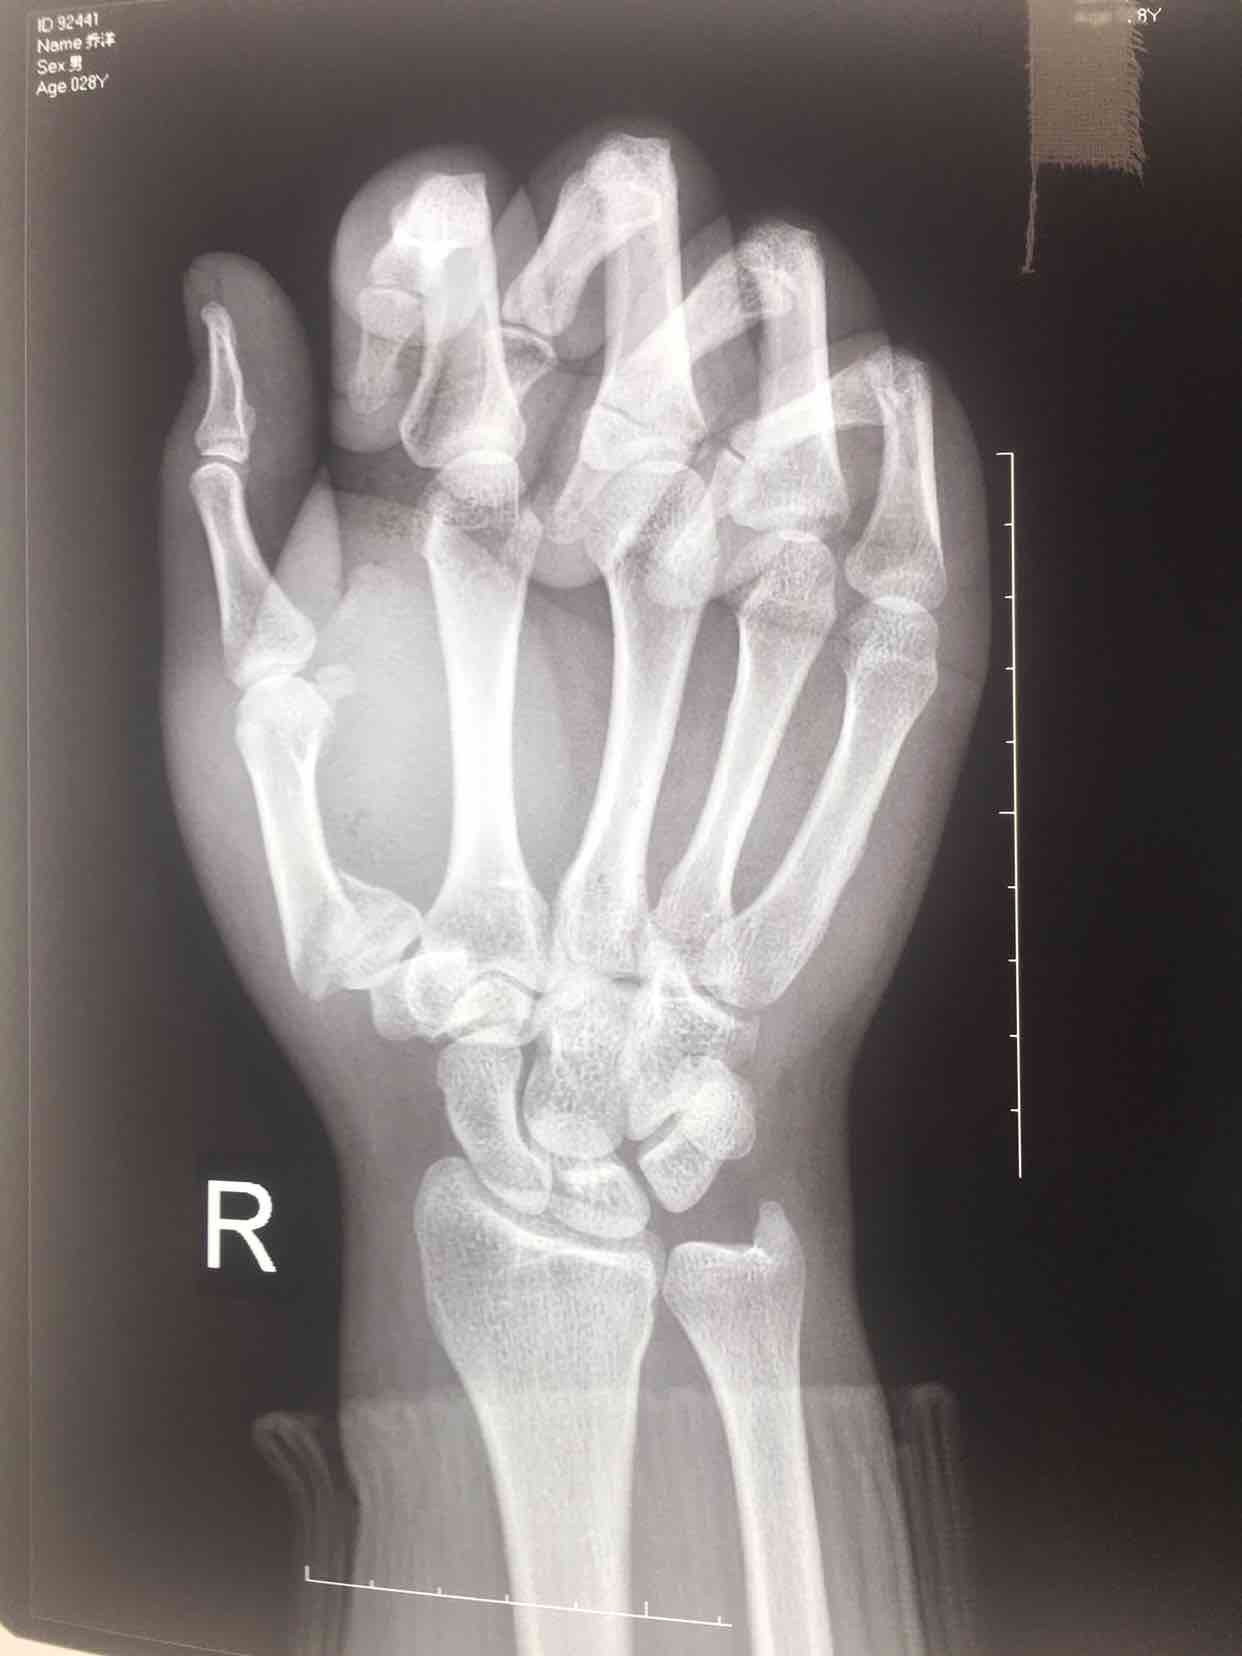

第一掌骨基底部骨折(微钢板固定)

摔伤后右手肿痛,活动受限2天入院。既往身体健康,无特殊不良嗜好。

生命体征平稳,心肺复未见异常。右手第一掌骨处肿胀明显,皮色青紫,皮下淤瘢,皮温正常,局部压痛明显,可及骨擦音及骨擦感,第一腕掌关节活动受限,末梢血运感觉正常。

诊断  第一掌骨基底部骨折在臂丛麻醉下行切复内固定术,术后石膏托固定,抗炎,消肿等处理。